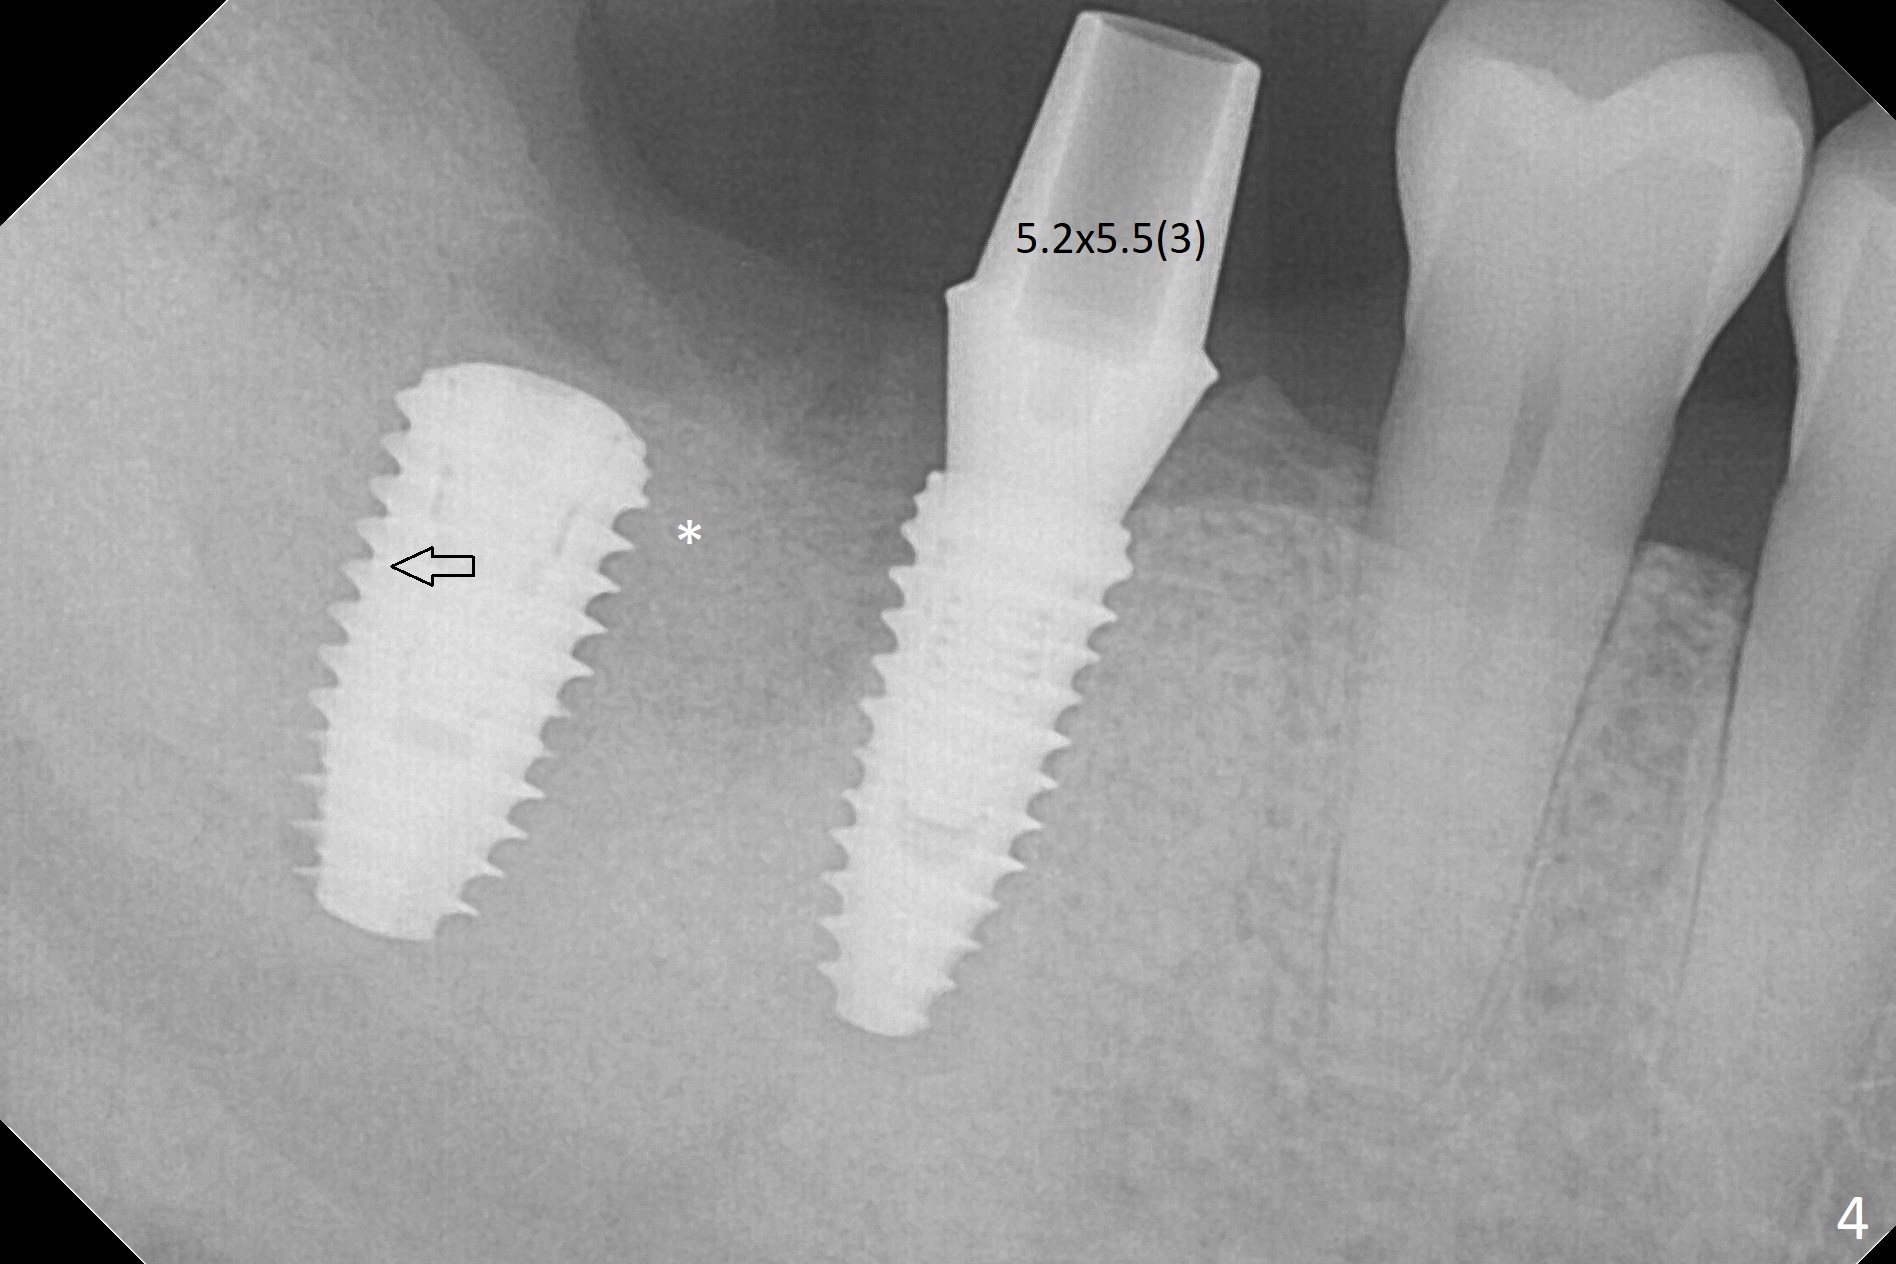

Osteotomy at the sites of #30 and 31 is initiated with Magic Split, followed by Magic Expanders (3.0 and 3.8 mm) at #31. Initial depth of osteotomy is 13 mm with 2.2 mm drill (Fig.1). After adjustment of the trajectory at #31 (Fig.1 arrow) and deepening the osteotomy by 2 mm, dummy implants are placed with stability (Fig.2). Following increase in osteotomy at #31, the larger implant in fact loses stability (Fig.3). The loose implant is pushed distal (Fig.4 arrow) with placement of autogenous bone mesial (*). The stable implant at #30 (Fig.3) and its abutment (Fig.4) are used as a post to hold periodontal dressing, which covers the wound at #31 after placement of collagen plug and suturing. In fact the same technique could be used when socket preservation was performed if an implant were placed at #30 at the same time. When the periodontal dressing dislodges, the wound at #31 heals uneventfully (Fig.5,6). The bone graft seems to remain in place 3 months postop (Fig.7). The implant is uncovered with placement of a 6.8x7 mm healing abutment 4 months postop. When a cementation abutment is placed and prepped, the buccal margin is much lower than the lingual (Fig.8 taken prior to cementation). The patient enjoys mastication with the new implant crowns 3.5 months post cementation (Fig.9).